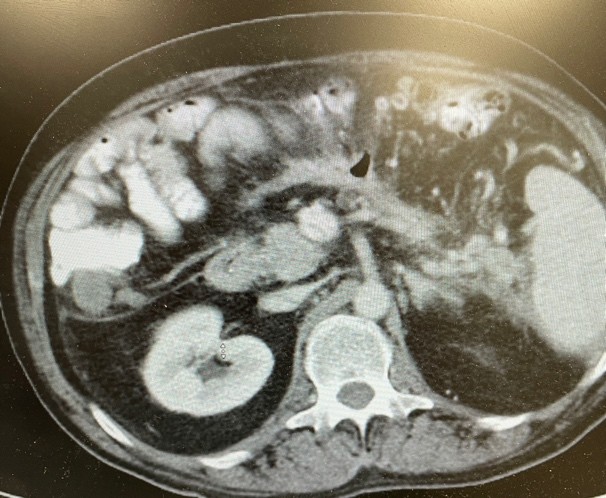

At the time of the initial EUS-guided drainage, the patient was only three weeks post-pancreatitis hospitalization. Due to the thin wall of the cavity, immediate necrosectomy was not performed since there was an increased risk of perforation. A week later he underwent necrosectomy. The procedure involved passing a double channel therapeutic scope into the esophagus and advanced into the stomach. EndoRotor powered endoscopic debridement catheter (Interscope), snare, and forceps were also used to remove the necroma from the cavity. The necrosectomy procedure had to be repeated three times due to the large size and mild bleeding to completely evacuate all the contents from the necrotic cavity. The repeat imaging showed complete healing and obliteration of the cavity and LAMS was successfully removed (Figure 2). There was a small left lower quadrant pelvic collection which could not be accessed by endoscopic ultrasound and was drained by the interventional radiologist. The drain was removed after complete resolution of the small collection. The patient returned to full time work and made a complete recovery without any sequela, such as kidney injury, lung injury or fistula formation.

Figure 4. Resolution of the necrotic cavity.

Figure 4